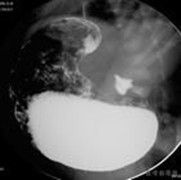

在有可疑病史的患兒可觸及“橄欖”,對於肥厚性幽門狹窄的診斷是足夠的。如果可疑的話,超聲檢查可證實幽門腫物的存在。超聲檢查的標準包括幽門直徑大於1.4cm,壁厚大於4mm。幽門管長度大於1.6cm。也可選擇鋇劑上消化道檢查(UGI),以證實診斷。診斷標準包括胃出口梗阻,有證明幽門管狹窄的“線”征,“肩”征或高度梗阻的幽門乳頭。如果使用UGI檢查,手術前應放人胃管,並用鹽水沖洗以去除鋇劑。糾正措施